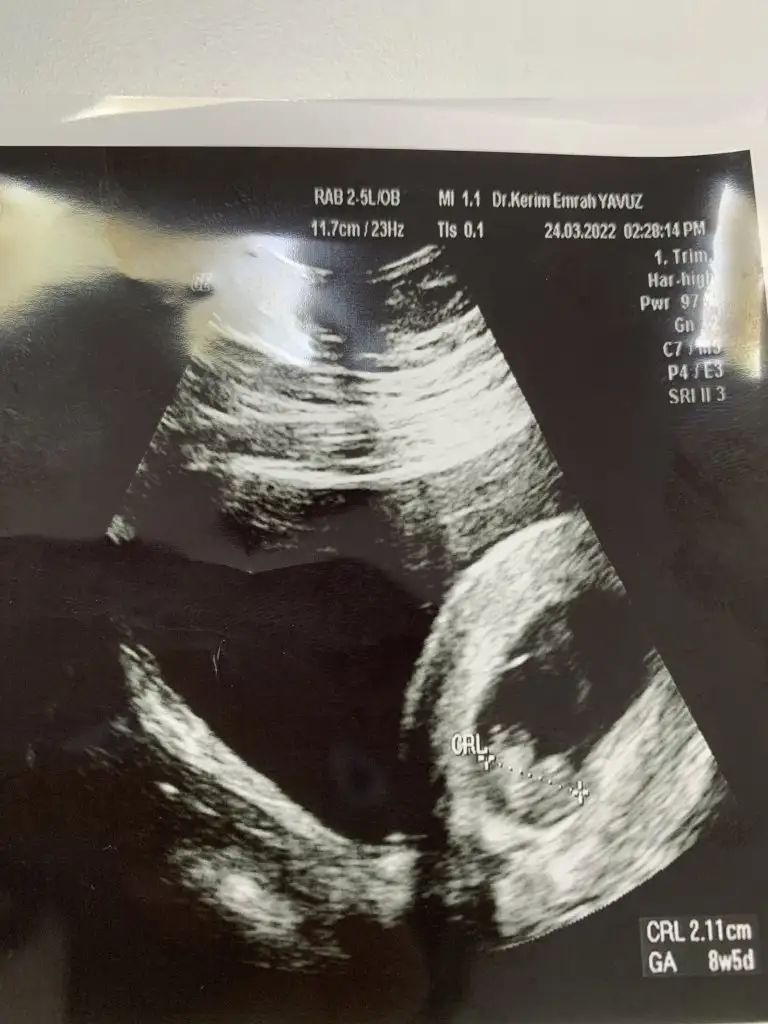

-Sunshine canım benim Kese görme tarihimi ve ilk kalp atışı tarihini ekleyebilir misin.

Kese görme 18.02.2022

Kalp atışı 01.03.2022

tarihleri ekliyorum